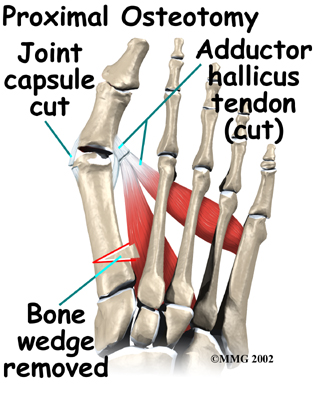

Proximal Osteotomy

In other situations, the first metatarsal is cut at the near end of the bone (called a proximal osteotomy.) This type of procedure usually requires two or three small incisions in the foot. Once the skin is opened the surgeon performs the osteotomy. The bone is then realigned and held in place with metal pins until it heals at which point the pins are removed. Again, this reduces the angle between the first and second metatarsal bones.

Realignment of the big toe is then done by releasing the tight structures on the lateral, or outer side of the first MTP joint. This includes the tight joint capsule and the tendon of the adductor hallucis muscle. This muscle tends to pull the big toe towards the middle of the foot. By releasing the tendon, the toe is no longer pulled out of alignment. The toe is realigned and the joint capsule on the side of the big toe closest to the other foot is tightened to keep the toe straight, or balanced.